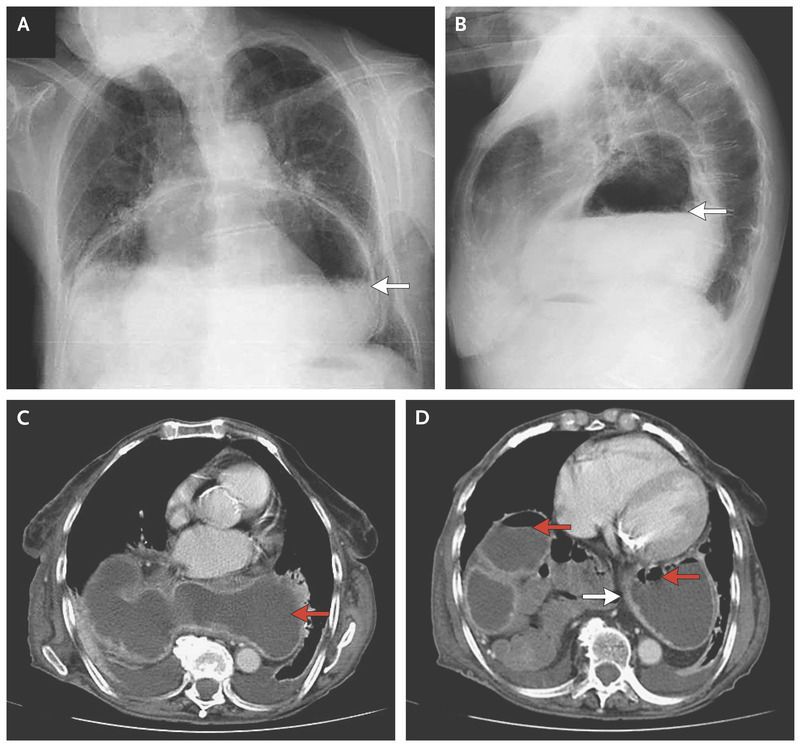

An 81-year-old woman with cerebrovascular disease presented to the emergency department with a 1-week history of vomiting. Findings on abdominal examination were notable for normal bowel sounds and the absence of tenderness, rebound, or guarding. A chest radiograph showed a large air–liquid shadow in the inferior retrocardiac position (Panels A and B, arrows), which suggested a large paraesophageal hernia. A computed tomographic scan showed a large retrocardiac mass containing air and liquid (Panels C and D, red arrows) that was consistent with herniation of the stomach into the chest. Thickening of the gastric wall suggested edema (Panel D, white arrow) and compression of the first portion of the duodenum, which caused gastric distention. Hiatal hernias are defined as protrusion of the stomach through the diaphragm into the chest. The degree of displacement can produce obstructive symptoms, as occurred in this patient, and may increase the risk of volvulus. Owing to her generally poor health status, the patient was treated conservatively, with gastric suction performed through a nasogastric tube followed by initiation and advancement of her oral diet, first with clear liquids, then soft foods, and finally solid foods. The vomiting resolved, and the patient was asymptomatic at the time of discharge.